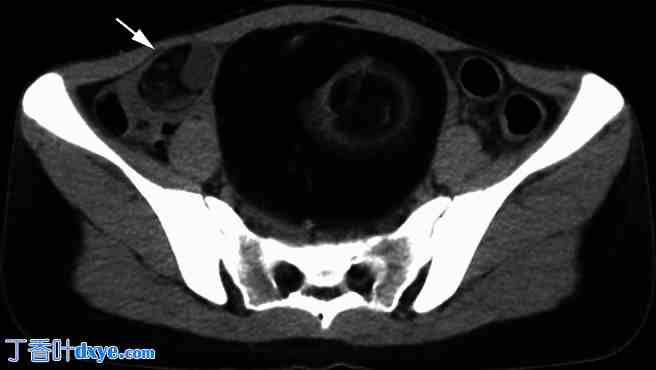

CT 扫描显示的右侧卵巢畸胎瘤。

术前平扫CT示右侧卵巢畸胎瘤长5 cm,内含脂肪及钙化部分,该畸胎瘤一年前长3 cm,如图1所示。